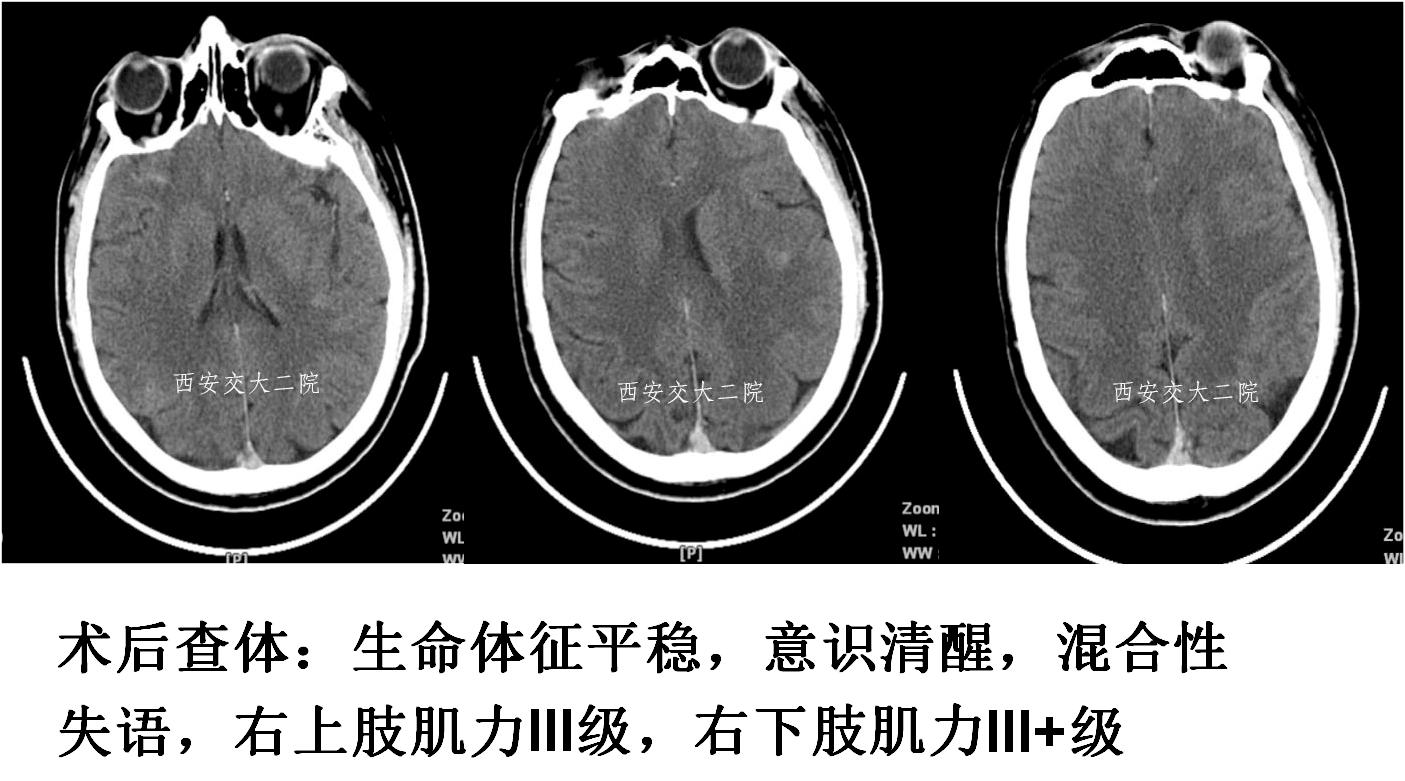

术后即刻病情及脑CT

术后24小时脑CT

术后病情变化

术后24h仍呈混合性失语,右侧肢体肌力Ⅴ-级。

术后48h言语恢复正常,右侧鼻唇沟略浅,四肢肌力Ⅴ级,转心外科继续准备手术。